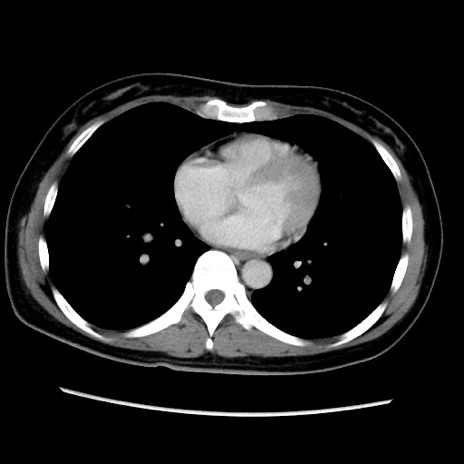

症例39(横断像)

【症例】40歳代女性

【主訴】上下腹部痛

【現病歴】2日目から下腹部痛あり。夜間は痛みで眠れなかった。昨日より上腹部痛と下痢が出現。臥位で痛みは軽快したため、休んでいた。本日になって臥位でも立位でも痛みが強くなってきたため救急要請。

【既往歴】子宮内膜症

【身体所見】部:平坦・軟、左上下腹部に圧痛あり、反跳痛あり。

【データ】WBC 21800、CRP 26.78